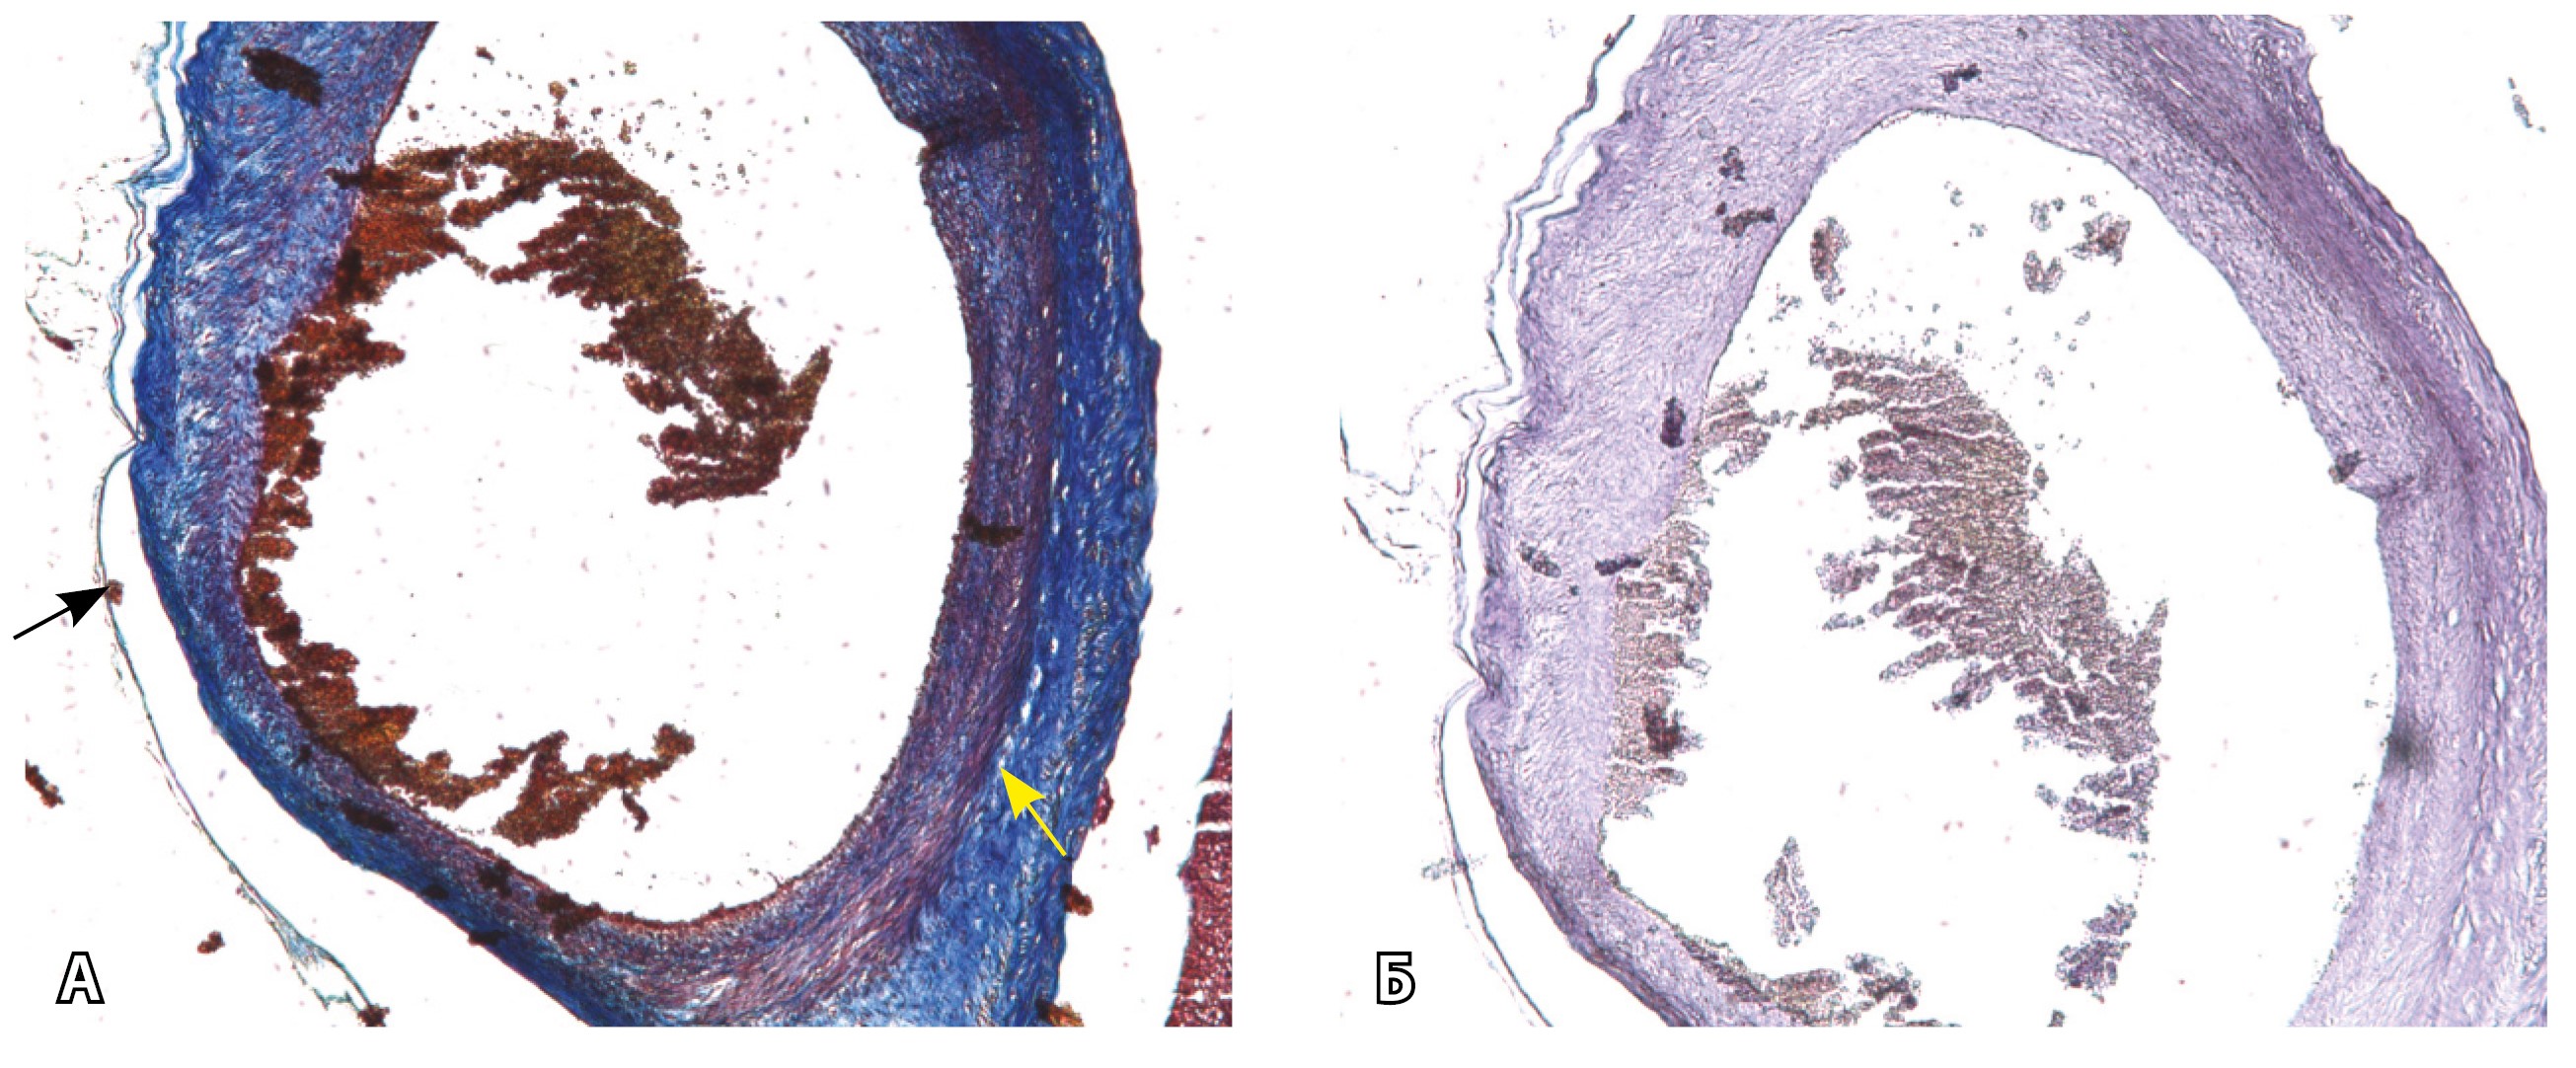

На микропрепаратах васкуляризация серозной оболочки представлена множеством крупных сосудов, идущих в разных направлениях и анастомозирующих друг с другом. Возможно, имеются артериовенозные соустья. На серийных срезах также видно, что в стенках артерий трудно различимы два слоя миоцитов (продольный и поперечный). Со стороны адвентиции они окружены толстым «футляром» из грубоволокнистой голубой ткани (при окраске по Маллори). Она проникает в стенку артерий, замещая мышечный слой (рис. 12).

Рис. 12. Истончение миометрия; в составе серозной оболочки видна крупная артерия, окруженная плотной соединительной тканью. А – cосуды в составе серозной оболочки (окраска по Маллори; × 200), не дифференцированная на мышечные оболочки стенка артерии, справа – вена, оба сосуда покрыты фиброзной оболочкой, внизу виден слой мезотелия в составе серозной оболочки; Б – серийный срез тех же сосудов при окраске на выявление эластических волокон, сосуд с соединительнотканной муфтой (окраска по Вейгерту; × 50): определяется полная дезорганизация эластичного материала в стенке; стрелкой указан мезотелий (аналог pl. increta, PAS 2 по FIGO)

Эластический каркас представлен сетью тонких волокон, без концентрации на внутреннюю и внешнюю мембраны. Однако маркер СD34 констатирует сохранение эндотелия, что свидетельствует о том, что по артериям циркулирует кровь, не сворачиваясь (рис. 13).

Рис. 13. Самые крупные сосуды в пределах серозной оболочки стенки матки: А, Б – серийные срезы артерии; × 50. При окраске по Маллори (А) видна тонкая полоска мезотелия (черная стрелка), слабо дифференцированная мышечная стенка артерии, вокруг нее – плотная коллагеновая оболочка (желтая стрелка), в просвете определяются тромботические массы. При окраске по Вейгерту (Б) наблюдается полная потеря внутренней и внешней эластических мембран

Главным отличием крупных сосудов в составе серозной оболочки является то, что морфологически они находятся в пределах стенки матки. Об этом свидетельствует наличие в операционном материале тонкого поверхностного слоя мезотелия, отделяющего матку от брюшной полости (рис. 11). Его невозможно визуализировать методом МРТ из-за особенностей метода и толщины получаемых срезов.

Сосуды 4-го типа встречались как при pl. increta (16,7%) (PAS 2 по FIGO), так и при pl. percreta (100%) в пределах серозного слоя матки (PАS 3a по FIGO). Обнаружено наличие крупных извитых анастомозирующих сосудов, преимущественно по поверхности матки, в сочетании с выраженным истончением рубца от КС. Главное отличие сосудов этого типа – локализация в пределах серозного слоя матки, с наличием тонкого поверхностного слоя мезотелия на микропрепаратах по их поверхности. Этот феномен можно объяснить тем, что в случае прикрепления трофобласта и затем плаценты к рубцу от КС при прогрессировании беременности плацента оказывает паракринное влияние в том числе посредством факторов ангиогенеза, в результате чего нельзя исключить рост сосудов из бассейнов маточных артерий с целью обеспечения трофической функции матки и сохранения беременности. Указанный патогенетический механизм также подтверждают описанные в литературе случаи брюшинной беременности [17]. Кроме того, нельзя исключить, что локальная ишемия стенки матки в области врастания может способствовать увеличению ангиогенеза и васкулогенеза. При выполнении МРТ невозможно достоверно визуализировать серозный слой матки из-за его малой толщины, поэтому создается впечатление о локализации сосудов за пределами стенки матки. По данным патоморфологического исследования, для этого типа характерно наличие крупных сосудов, анастомозирующих друг с другом. В стенках артерий трудно различимы 2 слоя миоцитов, по наружной поверхности сосуды окружены толстым «футляром» из грубоволокнистой соединительной ткани, которая проникает в стенку артерий и замещает мышечный слой. Эластический каркас представлен сетью тонких волокон, без концентрации на внутреннюю и внешнюю мембраны. Генез возникновения таких сосудов до конца не изучен. В ряде исследований, посвященных беременности, расположенной в проекции рубца от КС, отмечается наличие артериовенозных соустий по типу мальформации в данной области даже на ранних сроках беременности, которые, возможно, продолжают функционировать и на более поздних сроках и становятся еще более полнокровными [18–20].